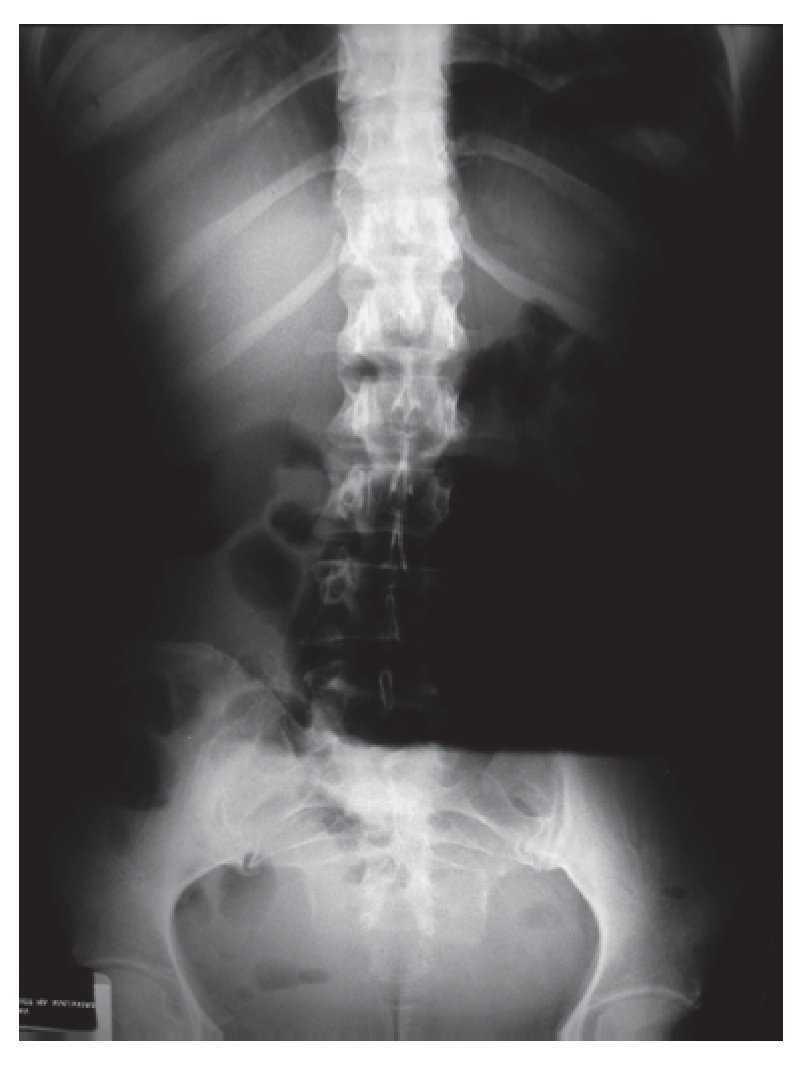

Paciente femenino de 46 años de edad, sin patológicos de importancia portadora de estreñimiento crónico de 26 años de evolución con autoprescripción. Inicia con dolor abdominal súbito de 2 días de evolución localizado en cuadrante inferior izquierdo, tipo cólico, sin náusea ni vómito, por lo que ingiere pancreatina con dimeticona sin mejoría, incrementando el dolor y agregándose náuseas, distensión abdominal e imposibilidad para canalizar gases, motivo por el cual acude a valoración. A su ingreso con vitales normales, con fascies de dolor, actitud forzada por dolor abdominal, mesomórfica. Mucosas parcialmente hidratadas, pálidas, cardiopulmonar sin alteraciones. Abdomen distendido, blando, doloroso a la palpación media y profunda de predominio en cuadrante inferior izquierdo, sin hiperestesia ni hiperbaralgesia. Rebote negativo. Peristalsis de lucha. Extremidades sin alteraciones. En radiografías simples de abdomen se observa distensión importante de colon proximal con nivel hidroaéreo en colon transverso y ausencia de gas en colon descendente y ámpula rectal (Imágenes 1 y 2). Se realiza colonoscopia con diagnóstico inicial de obstrucción colónica, introduciendo colonoscopio hasta una distancia de 120 cm, con lo que se llega a tercio distal de colon transverso impidiendo avanzar más el endoscopio por una zona de estenosis puntiforme, probablemente secundaria a torsión (Foto 1) intentando realizar detorsión sin éxito, por lo que es sometida a laparotomía exploradora encontrando torsión de colon transverso (Fotos 2 y 3) efectuando hemicolectomía derecha con transversectomía e ileosigmoideoanastomosis con engrapadoras, con una evolución favorable, siendo egresada al cuarto día por mejoría.

Foto 2. Torsión de colon transverso.

Foto 3. Colon transverso comprometido.

En este caso en particular se decidió realizar una hemicolectomía derecha con transversectomía secundario a la distención tan importante del ciego y cambios isquémicos secundarios.